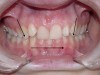

If the maxillary anterior teeth are positioned or inclined palatally, upon closure the lower teeth are going to first contact these teeth, which will force the mandible to shift to close into a retruded position. The objective is to try to identify this shift from primary contact to closure. This type of fence could potentially lead to shifting of the maxillary anterior teeth, breaking of the teeth, and/or muscular and jaw dysfunction as a result of posterior displacement of the mandible (Figures 2 through 5).

Figure 2

Figure 3

Figure 4

Figure 5